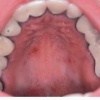

Lõhedega keel

(lingua plicata)

Umbes ühel protsendil vastsündinutest on keele pind limaskesta vagude poolt osadeks jagatud, mis jätab mulje, et keel on tavalisest punasem. Vanuse kasvades on leid pisut sagedasem.